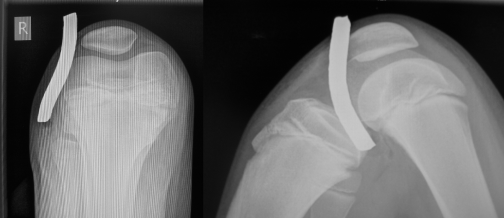

A 10-year-old boy while playing on a wall fell on the railing and sustained an injury to his right knee. He presented to casualty with a piece of metal protruding out of his flexed right knee. Primary and secondary survey did not reveal any other injuries. On examining the right knee there was a transverse laceration of about 4 cm at the level of lateral joint line with a rusted metal rod protruding out of the laceration (Figure 1a and Figure 1b). The knee was flexed at about 140° and no movement could be achieved due to pain. There was no distal neurovascular deficit. Rest of the right lower limb was normal. Radiographs showed a bent metal rod that appeared to be in the lateral compartment of the right knee (Figure 2). Patient underwent exploration of the wound and removal of the foreign body under general anaesthesia within 4 hours of the incident. Per-operative findings were show a dirty wound which was extended longitudinally, and the metal rod followed deep into the wound and removed. The metal rod had gone through the potential space between capsule and synovial lining of the knee joint. Exploration of this space did not show any breach of synovium (Figure 3). Thirty mL of Normal saline was infiltrated into the right knee from the superomedial aspect and there was no leakage of fluid into the space where the foreign body was found. The wound was thoroughly washed out and found to be clean. Intra-operative fluoroscopy showed no residual foreign body. The wound extension was closed. Patient was on intravenous broad-spectrum antibiotics for 48 hours and taken to theatre at 48 hours for a second debridement when it was found to be clean and a delayed wound closure was performed. Patient was allowed full weight bearing and range of movement exercises as tolerated. At 6 months follow up there was no evidence of infection in the wound. Patient had full range of movements in his right knee and no instability or features of meniscal pathology. He was back to playing football with no difficulties and hence, discharged from clinical care.

Figure 2: Radiographs of right knee. View Figure 2